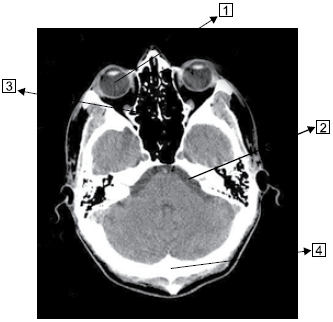

Observe a imagem a seguir.

Assinale a alternativa que corresponde às estruturas identificadas na imagem.